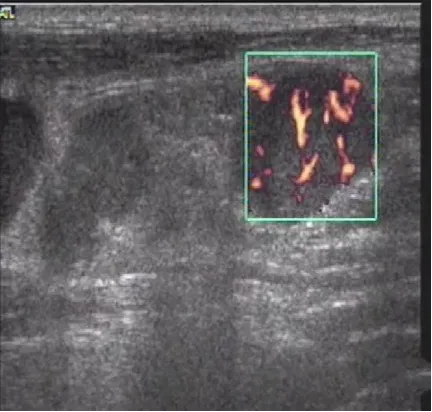

病例:左侧颈部无痛性结节2周,体检颈部可触及数个结节,可活动,无触痛。

超声描述:左侧颈部见数个肿大淋巴结,呈椭圆形,淋巴结之间无融合,大者约28x12mm,皮质增厚,髓质偏移,内部血流信号增多,呈树杈状分布。